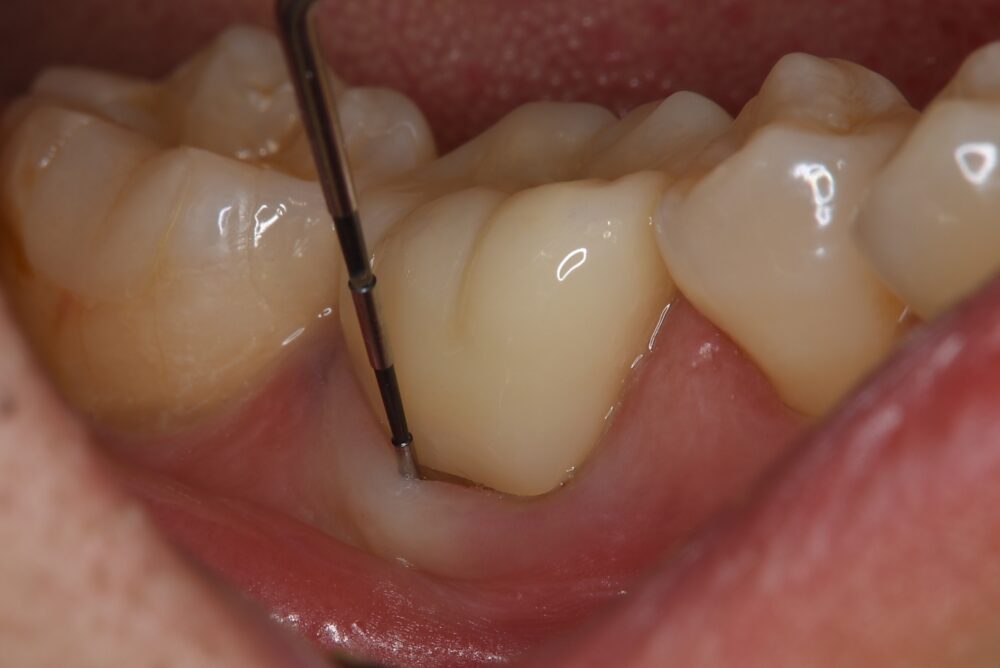

症例1:パーフォレーションリペア症例

(歯の中に大きな穴が空いてしまっているのを埋めて再生を促す治療)

歯に穴が空いていて骨に炎症がある状態 |

CTでも歯の周囲に骨がないのが分かる。 |

人為的根穿孔を起こした部分に感染を起こしており、歯周ポケットが9㎜ありました。 ラバーダム防湿とマイクロスコープを使用して丁寧に治療を行いました。 殺菌性があり歯を補強することのできるMTAという根管充填材料を使用して、歯周ポケットは2㎜に改善しました。 |